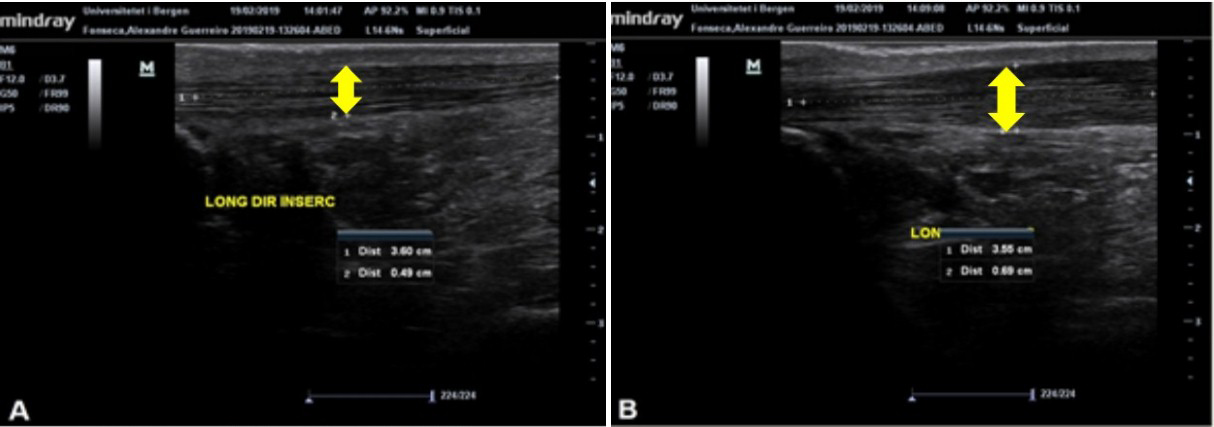

O tendão do calcâneo (TC) é o mais forte tendão do corpo humano, com grande capacidade de suportar carga. O TC é vulnerável a lesões por esforço repetitivo por receber muita carga, responsável por 18% de todas as lesões no esporte. O ultrassom (US) diagnóstico é uma técnica barata, dinâmica e rápida para avaliação de tecidos tendíneos, que pode ser associada a testes clínicos para diagnóstico de tendinopatias. Considerando que a simetria do organismo está relacionada com bom estado geral de saúde, objetivou-se neste trabalho avaliar a morfologia e aspectos clínicos do TC de indivíduos com e sem tendinopatia do TC. Participaram do estudo 28 indivíduos: 15 no grupo controle (GC) e 13 no grupo tendinopatia (GT). Os participantes passaram por avaliações específicas do TC: Exame de US, testes à palpação e clínicos. Os sujeitos do GC apresentam média de 0,407cm e 0,389cm da espessura do TC (TC direito e TC esquerdo), e não foram demonstradas anormalidades que indicassem inflamação nas imagens de US e nos testes clínicos. Nos indivíduos do GT, os valores da espessura do TC foram maiores, atingindo até 0,563cm, além de apresentarem alterações nas imagens de US para inflamação. A diferença da espessura do TC entre membros dos indivíduos do GC foi de 10%, enquanto no GT foi de 22%. Por meio dos resultados, sugere-se que diferenças da espessura do TC superiores a 20% indiquem a presença de tendinopatia, comprovadas pelos achados nas imagens de ultrassom e pelos resultados positivos dos testes à palpação e clínicos.Downloads